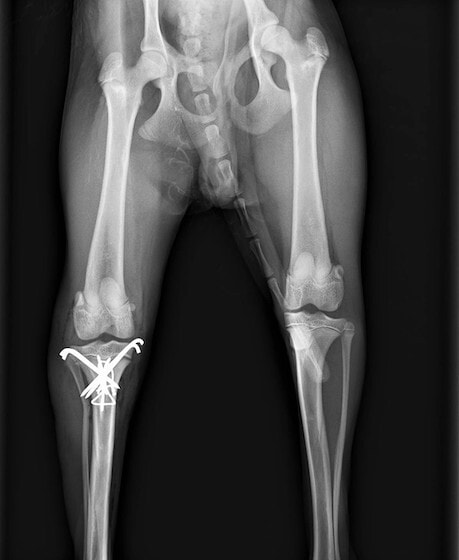

症例3:キルシュナーワイヤーのピンニングによる整復

ペルシャ猫 11ヶ月齢 雄

他院にて左大腿骨遠位の成長板骨折(salter-harrisⅠ型)が認められており、治療相談を目的として来院。当院にて、キルシュナーワイヤーを用いたピンニングにより骨折部位の整復を行いました。術後の経過は良好で、現在も経過観察中です。

術後レントゲン

機器

Arthrex社のターゲティングデバイスを用いてピンニングの位置を調整することで、確実な固定を行っています。当院ではこの手術器具以外にも、人の手術にも使用される様々な器具を導入し、手術精度を高め、また医療メーカーと新しい器具の開発、試作にも取り組んでおります。